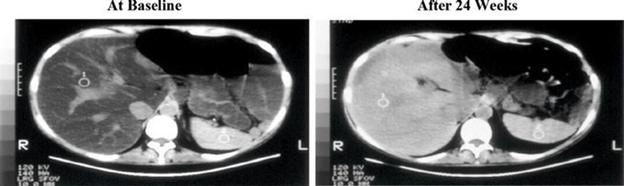

Figure 3. Liver CT Images: Before and After Treatment with IV Choline Chloride

Alkaline Phosphatase:

At baseline, LS mean ALP concentration was 239.3 ± 118.93 in the IV Choline Chloride group and 148.1 ± 100.2 in the placebo group. The mixed model for repeated measures, or MMRM, analyses demonstrated statistically significant decreases in ALP concentrations at Week 12 (p = 0.008), Week 16 (p = 0.005), Week 20 (p = 0.007), and Week 24 (p = 0.005) for the IV Choline Chloride group, demonstrating a reduction in cholestasis. A trend towards significance was observed at Week 4 (p = 0.076) and Week 6 (p = 0.056). At Week 34, 10 weeks after discontinuation of IV Choline Chloride treatment, LS mean change from baseline in ALP concentrations still demonstrated statistically significant decreases (p = 0.002), demonstrating a significant improvement in cholestasis with treatment with IV Choline Chloride (Figure 4).